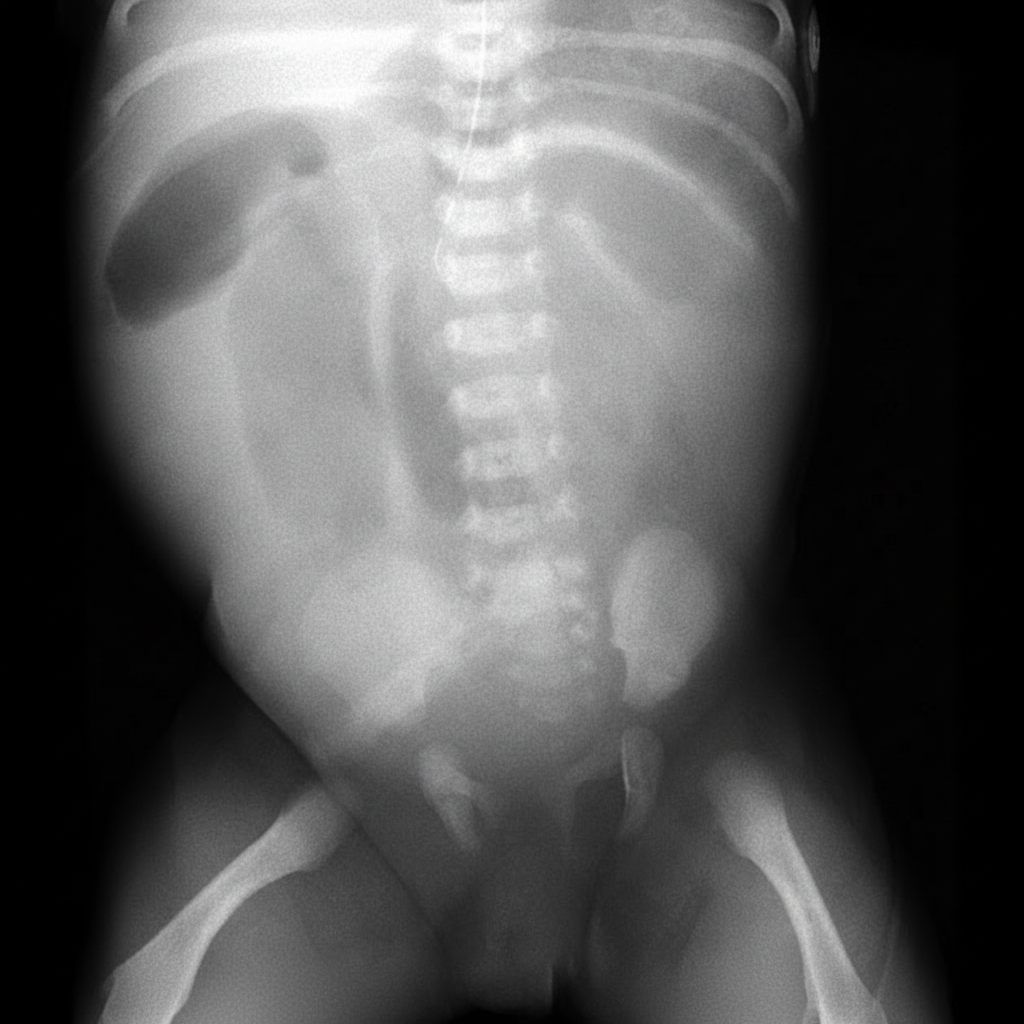

A 1-day-old baby boy has developed abdominal distension and bilious emesis. Prenatal history was significant for areas of echogenic bowel seen on ultrasound. An abdominal radiograph and contrast enema were performed. Based on these findings, what is the most likely diagnosis?

Explanation: ***Cystic fibrosis*** - **Prenatal echogenic bowel** combined with **neonatal bilious emesis** and **abdominal distension** on day 1 strongly suggests **meconium ileus**, which is pathognomonic for cystic fibrosis. - The **ground-glass appearance** on abdominal X-ray (**Neuhauser sign**) and **microcolon** on contrast enema are classic imaging findings confirming meconium ileus in cystic fibrosis. *Duodenal atresia* - Typically presents with **double bubble sign** on abdominal X-ray, showing dilated stomach and proximal duodenum. - While it causes **bilious vomiting**, it doesn't cause **echogenic bowel** on prenatal ultrasound or the specific imaging findings described. *Gastroenteritis* - **Not a day-1 neonatal diagnosis** as infectious gastroenteritis requires exposure to pathogens after birth. - Presents with **diarrhea** and **fever**, not the constellation of prenatal echogenic bowel and immediate postnatal bilious vomiting. *Malrotation with volvulus* - Diagnosed with **upper GI series/barium swallow** showing abnormal **ligament of Treitz** position and **corkscrew appearance** of twisted bowel. - While it causes **bilious vomiting**, it doesn't typically present with **prenatal echogenic bowel** or the specific contrast enema findings of microcolon.